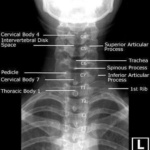

Las radiografías, generalmente llamadas rayos X, producen imágenes como sombras de huesos y ciertos órganos y tejidos. Las radiografías son muy buenas para detectar problemas óseos. Pueden mostrar algunos órganos y tejidos blandos; sin embargo, la MRI y la CT suelen crear mejores imágenes de los mismos. Aun así, las radiografías son rápidas, fáciles de obtener y menos costosas que los otros estudios, por lo que se pueden usar para obtener información rápidamente.

Un tubo especial dentro de la máquina de rayos X emite un haz de radiación controlada. Los tejidos del cuerpo absorben o bloquean la radiación en diferentes grados. Los tejidos densos como los huesos bloquean la mayor parte de la radiación, pero los tejidos blandos, como la grasa o los músculos, bloquean menos radiación. Después de pasar por el cuerpo, el haz alcanza una pieza de un fragmento de película o un detector especial. Los tejidos que bloquean altas cantidades de radiación, como los huesos, aparecen como áreas blancas en un fondo negro. Los tejidos blandos bloquean menos radiación y aparecen en tonos de gris. Los órganos que contienen principalmente aire (como los pulmones) aparecen en negro. Los tumores son por lo general más densos que el tejido que los rodea, por lo que suelen verse en tonos grises más claros.